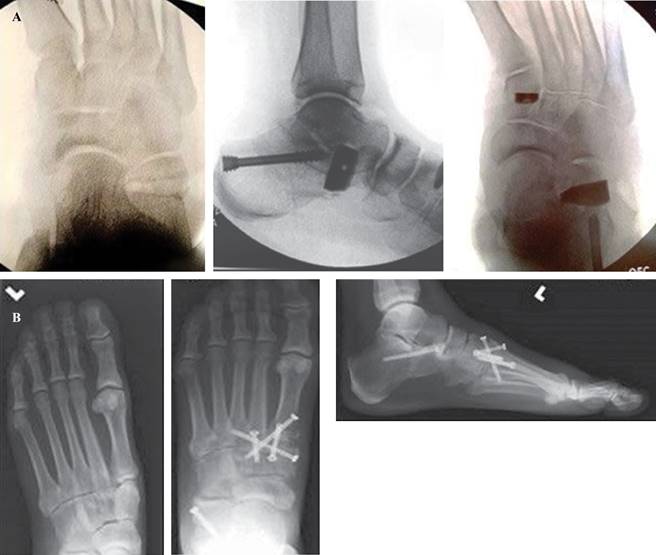

Técnica quirúrgica: la incisión se inicia por debajo del maléolo lateral en un ángulo aproximado de 45 grados, evitando el nervio sural y sus ramas así como los tendones peroneos. La disección continúa hasta el hueso, los separadores de Hohmann se colocan en posición dorsal y plantar alrededor del hueso para proteger las estructuras y los tejidos blandos. La osteotomía se realiza controlando la profundidad de la sierra, asegurándose de no penetrar en la cortical medial. Se puede usar un osteótomo para completar el corte de la cortical medial y un separador laminar para abrir la osteotomía y estirar el periostio medial permitiendo un mayor desplazamiento. Con el pie en flexión plantar la osteotomía se fija temporalmente con agujas de Kirschner. El calcáneo se desplaza aproximadamente 1 cm y luego se verifica con imágenes radiográficas axiales. La fijación se realiza generalmente con un tornillo canulado de 6.5 mm o una placa en «escalera» lateral (Figura 7).

Figura 8: Osteotomía de Evans, A) asociada a osteotomía de la primera cuña. B) Asociada a artrodesis de Lisfranc.